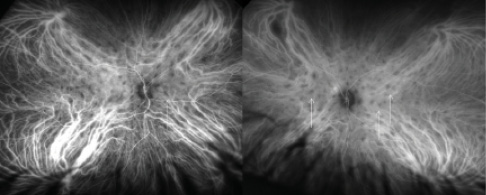

Figure 5. A 40-year-old white woman presented with decreased vision and photopsia in each eye. ICGA showed multiple subretinal hypofluorescent birdshot (vitiliginous) lesions in each eye (arrows). Lab workup revealed the presence of HLA-A29+.

Figure 6. A 34-year-old black man presented with a 5-week history of blurry vision and photosensitivity in each eye. The presence of subretinal hypofluorescent lesions was noted in each eye with ICGA. Chest x-ray confirmed the presence of hilar lymphadenopathy and a diagnosis of sarcoidosis.